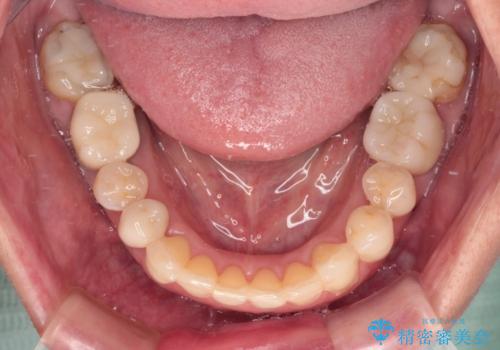

欠損やむし歯の歯をきれいなセラミックに 全顎虫歯治療

- 他院で矯正治療を終えたものの、むし歯や欠損部の治療が進められないとのことで来院された患者様です。

欠損部や、銀歯やむし歯の大きな歯はセラミッククラウンやブリッジに、小さいむし歯はセラミックインレーにて治療を行うこととしました。

歯肉の状態がとても、短期間でスムーズに治療を終えることができました。